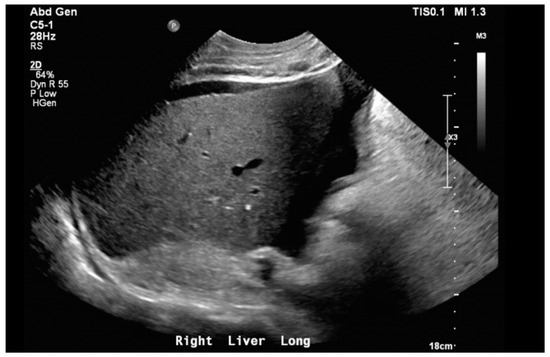

Notable normal admitting lab values included the following: aspartate aminotransferase, alanine transaminase, alkaline phosphatase, bilirubin, platelet count, and international normalized ratio. Creatinine on arrival was 0.79 mg/dL and white blood cell count was 6.0 cells/μL. The only noteworthy abnormal lab was an elevated brain natriuretic peptide of 864 pg/mL. Venous blood gas on arrival with pH of 7.353, pCO2 55.9 mmHg, HCO3 31.1 mmHg, and pO2 21 mmHg. Large-volume paracentesis was performed (5 L), with fluid analysis revealing a serum–ascites albumin gradient (SAAG) of 1.2 g/dL and total protein of 2.6 g/dL. The total nucleated cell count was 1020 cells/mm3 with a polymorphic nucleated cell count (PMN) of 663 cells/mm3, consistent with SBP. The bacterial culture of peritoneal fluid did not grow any organism. An abdominal ultrasound revealed nodular contours within the liver and heterogeneous echotexture compatible with cirrhosis (Figure 1). Doppler imaging of the liver showed patent vessels. Repeat TTE on this admission showed a preserved EF of 65% with paradoxical septal motion, flattened interventricular septum, and severe right ventricular (RV) enlargement consistent with RV pressure/volume overload. The pulmonary systolic pressure was estimated at 74 mmHg (Figure 2). Additionally, the patient was found to have moderate tricuspid regurgitation with a maximum velocity of 385 cm/second (Figure 3).

Figure 1. Liver ultrasound in right long axis demonstrating nodular contours with coarsened echotexture. Moderate volume ascites can also be seen.